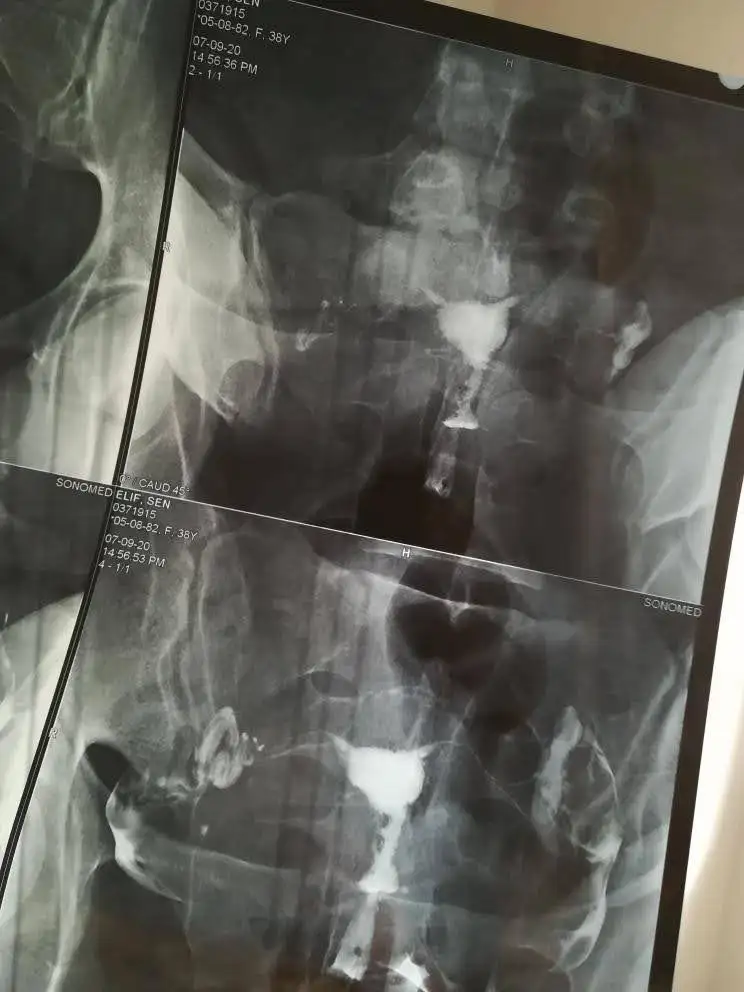

Benim hikayem burda detayları okumak istersen. 1 tüp bebk negatifim var 2.ye hazırlanırken hamile kaldım. O arada histereskopi olmuştum. Rahim filmim ilk sayfada bak bakınca anlarsın sen de zaten. Filmime bakan bir ton doktor oldu aralarında prof da dahil. Herkes normal dedi. Tüp bebek doktorum Eray Çalışkan'dı. O dedi bak rahminde bir problem var bu yüzde elli düşüğe sebep olur. Genelde 2 düşük sonrası histereskopi ila düzeltilir dedi. Tam redaviye başlayacağımız gün öğrendik. Bir şey diyemedik. Allah'a emanet dedik başladık. Bende amh düşük. Tek embriyom oldu transfer oldu. O da negatif sonuçlandı. Ardından hocaya hemen histereskopi istiyoruz biz düşük riskini almak istemiyoruz dedik. Ve rahme atılan çizik gebe kalma ihtimalini arttırdığı için de istiyoruz dedik. O da çok doğru karar dedi keşke herkesr yapsak dedi. Çünkü hsgde görünmeyen perde polip varsa onlar da temizlenecekti. Neyse ki sorun çıkmadı başka tepedeki çıkıntı giderildi. Operasyonumu Bertan Akar yaptı. Özel Kocaeli Hastanesi'nde. Eray hoca o da yapabilir dedi maddi olarak biraz daha uyguna geleceği için onu seçtik bu süreçte maddiyat da düşünmek gerekiyor. Şubatta histereskopi oldum. Mart sonu regl olunca 2. Tüp bebek denememi yapacaktım. Hamile kalmışım.